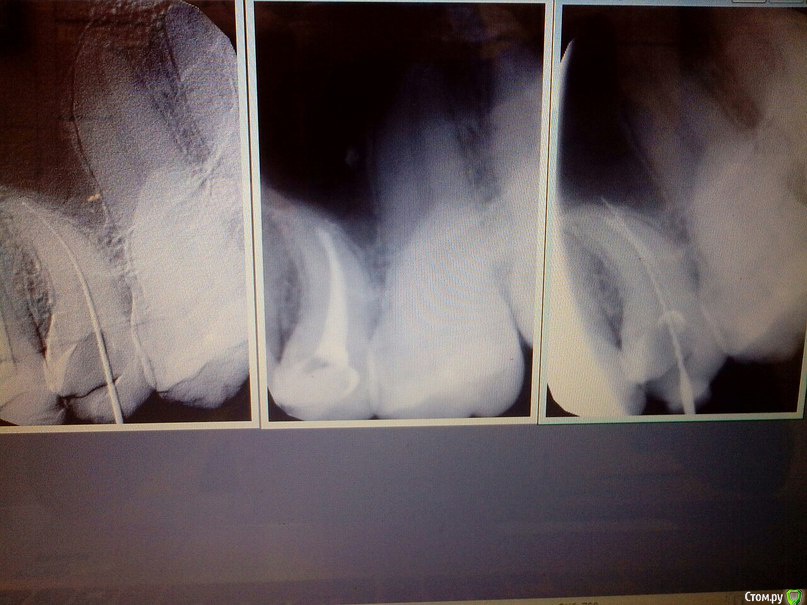

gusar7770 Опубликовано 12 июля, 2015 Поделиться Опубликовано 12 июля, 2015 Коллеги прошу помощи в непростой ситуации.25 зуб лечен мной по поводу пульпита,решил перепломбировать и как итог перфо,оставил под кальцием.Вопрос как можно обойти перфорацию,у меня в голове только расширение по малой кривизне с попыткой закрытия перфорации прорутом и допломбировкой канала.Для себя сделал несколько выводов,не работать протейперами в изогнутых каналах,и стараться использовать гипохлорит,тк с ЭДТА возможен риск транспортации. Ссылка на комментарий

gusar7770 Опубликовано 15 июля, 2015 Автор Поделиться Опубликовано 15 июля, 2015 (изменено) Коллеги всем спасибо большое за советы,сегодня запломбировал перфо proroot-ом,выкладываю вообщем что получилось.По моим ощущениям у зуба один большой магистральный канал,с "развилкой" в нижней трети.(на первом снимке хорошо видно).Пациента постараюсь отправить на 3д,чтобы визуализировать дальнейшие проблемы и сюрпризы и заодно посмотреть "мою головную боль") Ребят у меня вопрос,при каких размерах перфорации вы используете стандартную технику(оставляете как есть)и при каких случаях перфовы используете мта,прорут,триоксидент,отчего зависит выбор метода? Изменено 15 июля, 2015 пользователем gusar7770 Ссылка на комментарий

Bratok Опубликовано 27 июля, 2015 Поделиться Опубликовано 27 июля, 2015 Мне одному кажется что там 2 канала? Возможно боль обусловлена пустым каналом. Обратите внимание на верхушку корня, за ней точно кто то прячется хотя может это у меня воображение разыгралось. Ссылка на комментарий